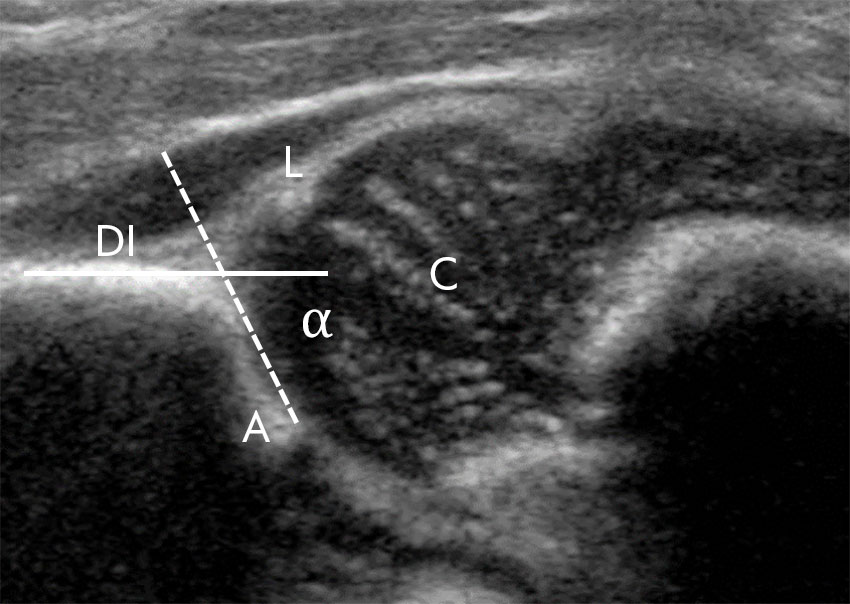

Alle 22 inviterte avdelinger besvarte undersøkelsen. Alle avdelinger tilbød selektiv ultralydscreening, hvorav 15 (68,2 %) ved radiolog (tabell 1). Lege i spesialisering i barnesykdommer utførte den kliniske hofteundersøkelsen ved 17 av de 22 avdelingene, hvorav 7 avdelinger (42 %) stilte krav til kompetanse før selvstendig utførelse. Tidspunkt for selektiv ultralydscreening varierte fra 0 til 12 ukers alder (tabell 1). Ultralydundersøkelse av hofter ble utført med en kombinert teknikk (der acetabulums form og caputs stabilitet ble vurdert separat) ved 16 avdelinger (72,7 %) (tabell 1). 21 avdelinger benyttet alfavinkelen (figur 1) som mål for acetabulums skålform, mens 11 målte caputs dekningsgrad, enten alene eller i tillegg til alfavinkelen.

Acetabulums helningsvinkel (alfavinkelen) ble målt og benyttet for klassifisering av hoften som normal, umoden, lett dysplastisk eller alvorlig dysplastisk ved alle sykehus bortsett fra ett, som kun målte caputdekning. Dette er oppløftende, idet alfavinkelen er den best validerte og mest presise markøren for dysplasi i nyfødtperioden (11). Det er også funnet godt samsvar mellom en normal alfavinkel ved tre til fire måneders alder og acetabulær indeks målt på røntgen ved tolv måneders alder (12). Dynamisk ultralyd uten bruk av morfologiske mål har på den annen side vist dårlig samsvar med senere røntgenfunn (13). Tilsvarende undersøkelser for mål av prosentvis caputdekning er ikke publisert, og den prognostiske verdien av dette målet er derfor uklart.